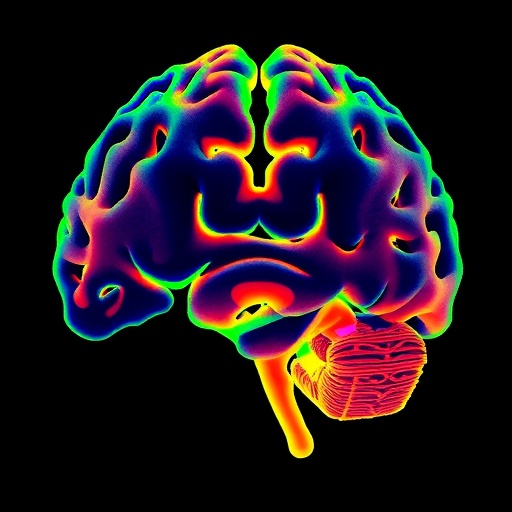

In a groundbreaking study published in Experimental & Molecular Medicine, a team of neuroscientists has unveiled the pivotal role of cerebellar tonic inhibition in orchestrating the maturation of information processing and motor coordination. The cerebellum, long recognized for its critical involvement in fine-tuning motor commands and maintaining balance, has now been shown to rely on complex inhibitory mechanisms to develop its functional capabilities fully. This work opens new avenues for understanding neurodevelopmental processes and sheds light on potential therapeutic targets for motor dysfunction.

The brain’s cerebellum has traditionally been studied for its contributions to movement precision and timing; however, the intricate cellular and molecular processes that underlie its maturation remain incompletely understood. Tonic inhibition, a form of persistent inhibitory signaling mediated mainly through extrasynaptic GABA_A receptors, suppresses neural excitability in a sustained manner, contrasting phasic inhibition which is rapid and transient. The research team led by Kwon et al. has elegantly demonstrated that this sustained inhibitory tone is indispensable for the developmental refinement of cerebellar circuits and their output functions.

At the core of their study lies the meticulous dissection of GABAergic mechanisms within cerebellar granule cells and Purkinje neurons. Granule cells, the most numerous neurons in the brain, form the input layer of the cerebellar cortex, while Purkinje cells serve as the main output neurons, sending inhibitory signals to deep cerebellar nuclei. By employing a combination of electrophysiological recordings, molecular biology techniques, and behavioral assays, the investigators established that tonic inhibition modulates the maturation timeline of these neuronal populations, ultimately sculpting the cerebellar information processing landscape.

Through high-resolution imaging and electrophysiological mapping, the team documented that tonic inhibition influences not only the firing properties of individual neurons but also the overall oscillatory dynamics within cerebellar circuits. Such oscillations are critical for timing-dependent synaptic plasticity, which in turn governs the adaptive adjustments in motor learning and coordination. The findings propose that tonic inhibition serves as a fundamental neurophysiological mechanism coordinating both cellular and network-level maturation.